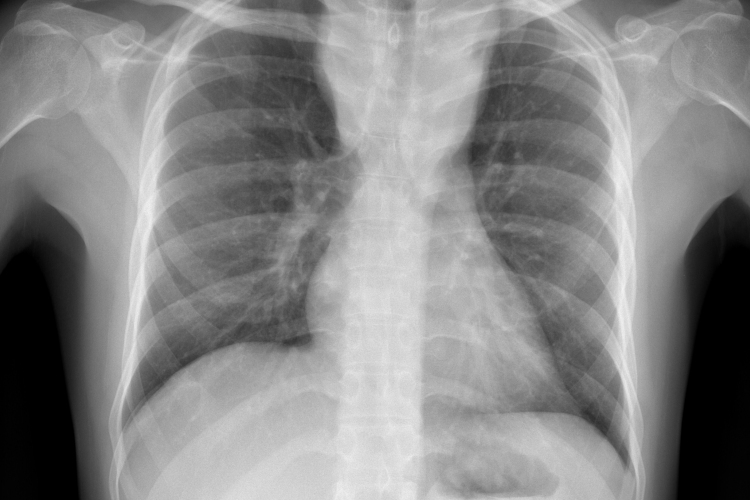

Csökkent a tbc-fertőzések száma Európában

Átlagosan 4,3 százalékkal csökkent az új tuberkulózisos (tbc-s) esetek száma 2010 és 2014 között az Egészségügyi Világszervezet (WHO) 53 országot magába foglaló európai régiójában.